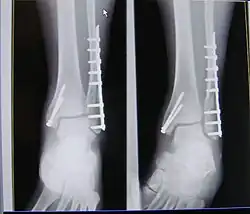

X-ray of trimalleolar fracture repair with plate and nails

Surgical repair using open reduction and internal fixation is generally required, and because there is no lateral restraint of the foot, the ankle cannot bear any weight while the bone knits. This typically takes six weeks in an otherwise healthy person, but can take as much as twelve weeks. Non-surgical treatment may sometimes be considered in cases where the patient has significant health problems or where the risk of surgery may be too great.[1]